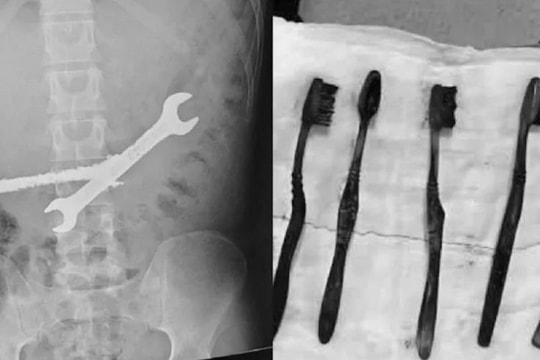

Bé trai 7 tuổi xẹp phổi trái, bác sĩ gắp ra thứ "đáng sợ" bên trong

16/02/2026 02:00

Bé trai 7 tuổi ở Nghệ An nhập viện trong tình trạng khó thở, tím tái. Bác sĩ ngay lập tức lấy thành công mảnh nhựa sắc nhọn, kịp thời ngăn suy hô hấp và biến chứng nặng.